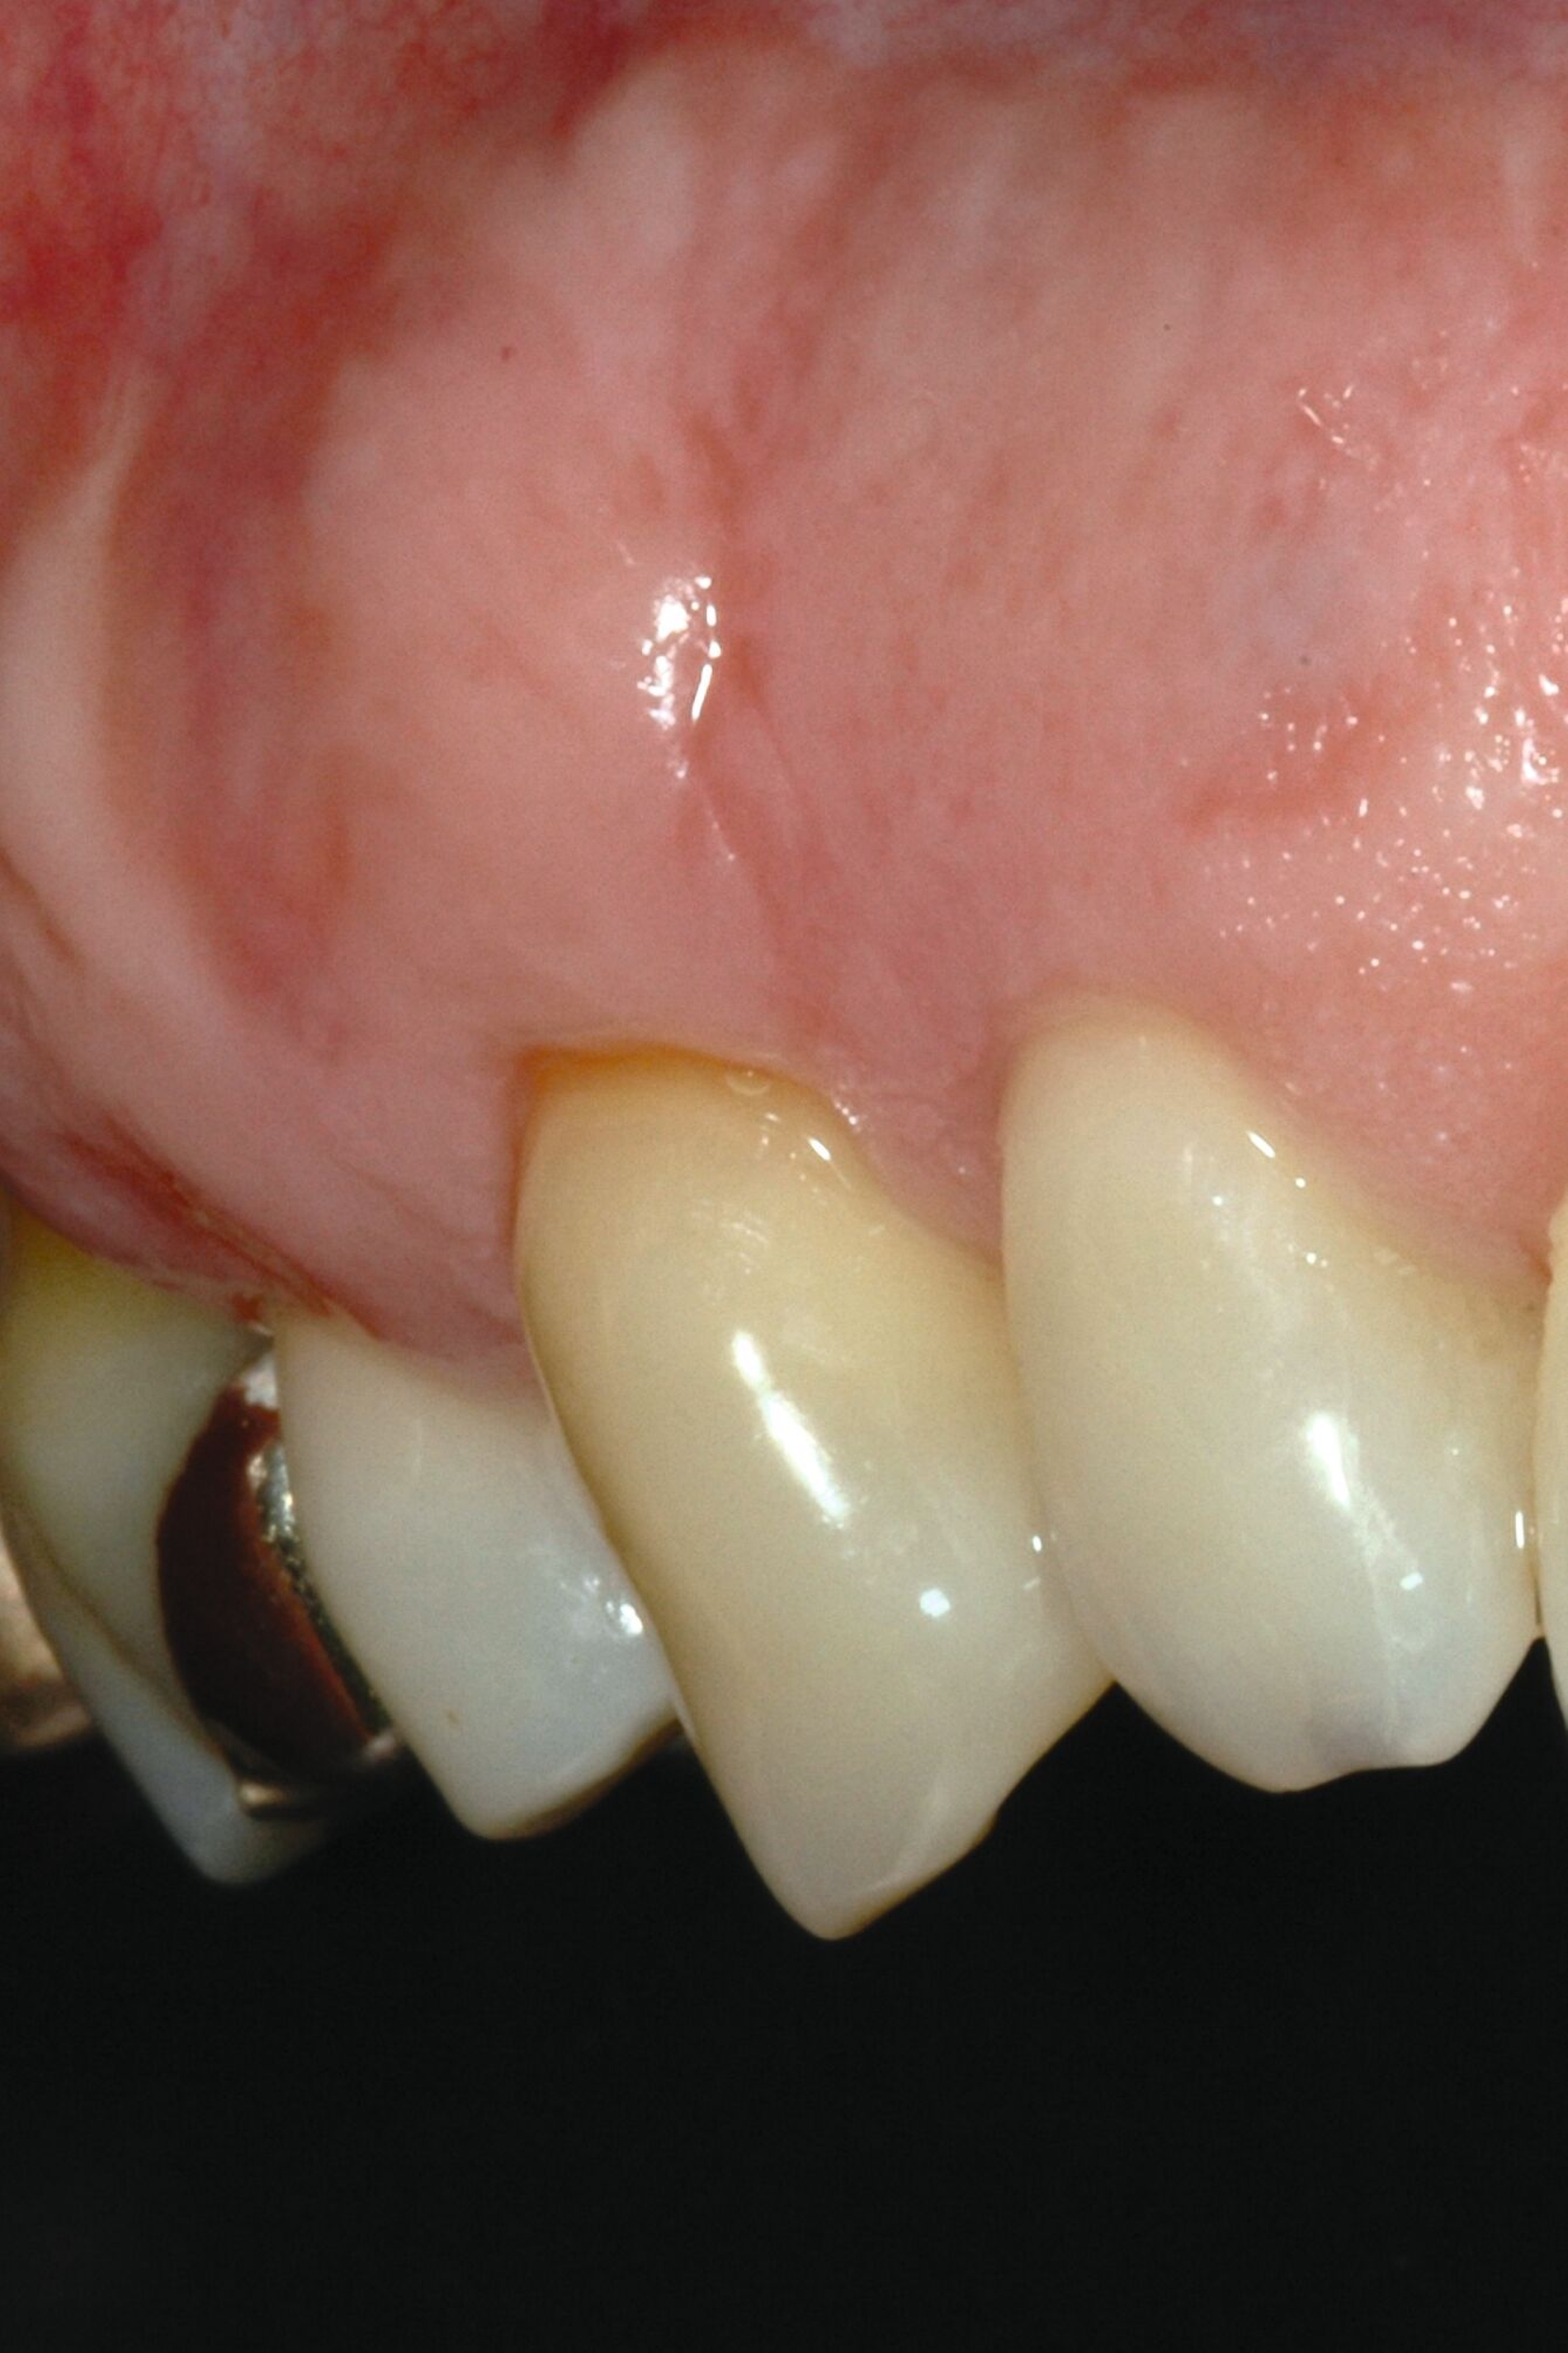

Schon in der Mitte des 20. Jahrhunderts wurden die ersten lateralen Verschiebelappentechniken zur Deckung parodontaler Rezessionen beschrieben. Grupe & Warren veröffentlichten 1955 die erste Beschreibung eines lateralen „sliding flap“ zur Deckung einer singulären parodontalen Rezession [Grupe und Warren, 1956]. Bei dieser Methode wurde das distal von der Rezession gelegene Gewebe einschließlich des bukkalen benachbarten Papillenanteils gelöst und die Gingiva im Bereich der Rezession exzidiert. Anschließend wurde dieser Lappen nach mesial verschoben, so dass der Papillenanteil direkt wieder im Bereich der benachbarten Papille fixiert und die freiliegende Wurzeloberfläche abgedeckt wurde. Großer Nachteil dieser unilateralen Verschiebelappen sind die hohen Rückstellkräfte aufgrund der ausgeprägten Verschiebung in eine Richtung um circa eine Prämolarenbreite. Daher zeigen laterale Verschiebelappen eine hohe Rezidivtendenz mit geringer prozentualer mittlerer Wurzeldeckung von 34 bis 82 Prozent, die zwar durch den zusätzlichen Einsatz eines Bindegewebstransplantats mit 70 bis 98 Prozent deutlich verbessert wird, aber durch die ausgeprägten Spannungen zu einer erhöhten Narbenbildung führt, die auch nach Jahren deutlich sichtbar sein kann (Abbildung 1) [Pagliaro et al., 2003]. Zudem führte die Verschiebung der keratinisierten Gingiva an den Nachbarzähnen nicht selten zu einer parodontalen Rezession an diesen, so dass Grupe in einer weiteren Publikation empfahl, die marginale Gingiva der Nachbarzähne in den Verschiebelappen nicht mit einzubeziehen [Grupe, 1966]. Pfeifer & Heller empfahlen in ihrer Analyse zur Vermeidung von Rezessionen an den Nachbarzähnen anstatt vollschichtiger Lappen teilschichtige Präparationen durchzuführen [Pfeifer und Heller, 1971].

Aus diesem Grund kann die Nelson-Technik dahingehend verändert werden, dass die Läppchen verlängert werden, indem diese am Sulkus der Nachbarzähne vorbeigeführt werden und die Entlastung nicht als senkrechte Inzision, sondern in Form eines runden Rückschnitts zur Rotation der Lappen geführt wird (Abbildung 2). Dies erleichtert auch die vollständige Deckung des OP-Gebiets, so dass keine sekundäre Granulation im lateralen Bereich erforderlich ist (Abbildung 2d). Auch bei guter Heilung zeigt sich aber eine ausgeprägte Narbenbildung direkt im Bereich des gedeckten Zahnes, insbesondere bei singulären Rezessionen. Zudem kommt es zu deutlichen Veränderungen von Textur und Farbe im Bereich der mukogingivalen Grenze, die ebenfalls das ästhetische Ergebnis stark beeinträchtigten (Abbildung 2e).